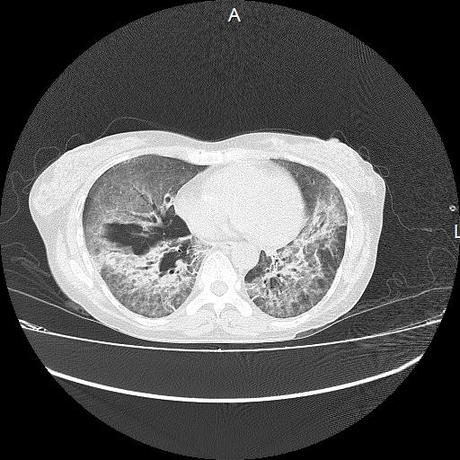

El parénquima pulmonar con areas parcheadas difusas en vidrio despulido combinadas con otras areas hipodensas de baja atenuación debidas a atrapamiento aéreo y engrosamiento intersticial y zonas de fibrosis de predominio en lóbulos medios e inferiores de ambos pulmones.

- LOS HALLAZGOS PUEDEN ESTAR EN RELACIÓN A NEUMOPATIA INTERSTICIAL PROBABLE ETIOLOGIA HIPERSENSITIVA VS AUTOINMUNE/BACTERIANA/FUNGICA.